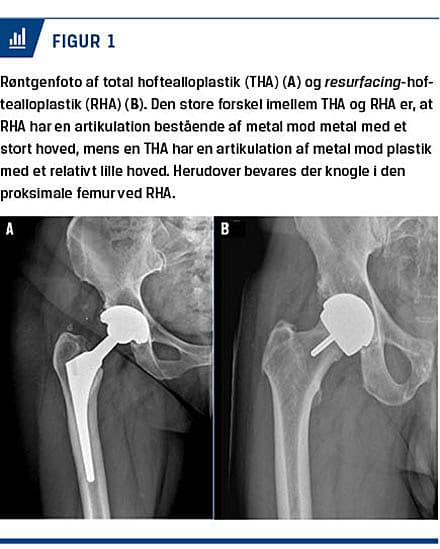

Princippet bag RHA er at forsøge at bevare den oprindelige anatomi og biomekanik. Det store hoved nedsætter teoretisk risikoen for ledskred og slid. For lårbenets vedkommende fjernes kun en mindre del af caput femoris, samtidig med at collum og den proksimale femur lades urørt. Teoretisk er dette en fordel, da man vil kunne foretage en senere revision med anvendelse af et standardstem i en urørt knogle [1, 5] (Figur 1).

Acetabulum præpareres som ved en standard-THA. Ved RHA bevares derfor hoftens naturlige biomekanik, hvilket nedsætter risikoen for stress-shielding (manglende belastning, der medfører knogletab) af den proksimale femur. Ledfladerne på en RHA består af metallegeringer, hvor krom (Cr) og kobolt (Co) er de vigtigste metaller. RHA og THA kan udføres i samme operative adgang, hvilket i Danmark typisk er en bagre adgang [1]. Ud over ovennævnte biomekaniske forhold er den store forskel imellem THA og RHA selve artikulationen, som ved en RHA er MoM med et stort hoved, mens det ved en THA som oftest er metal mod plastik med et relativt lille hoved (Figur 1).